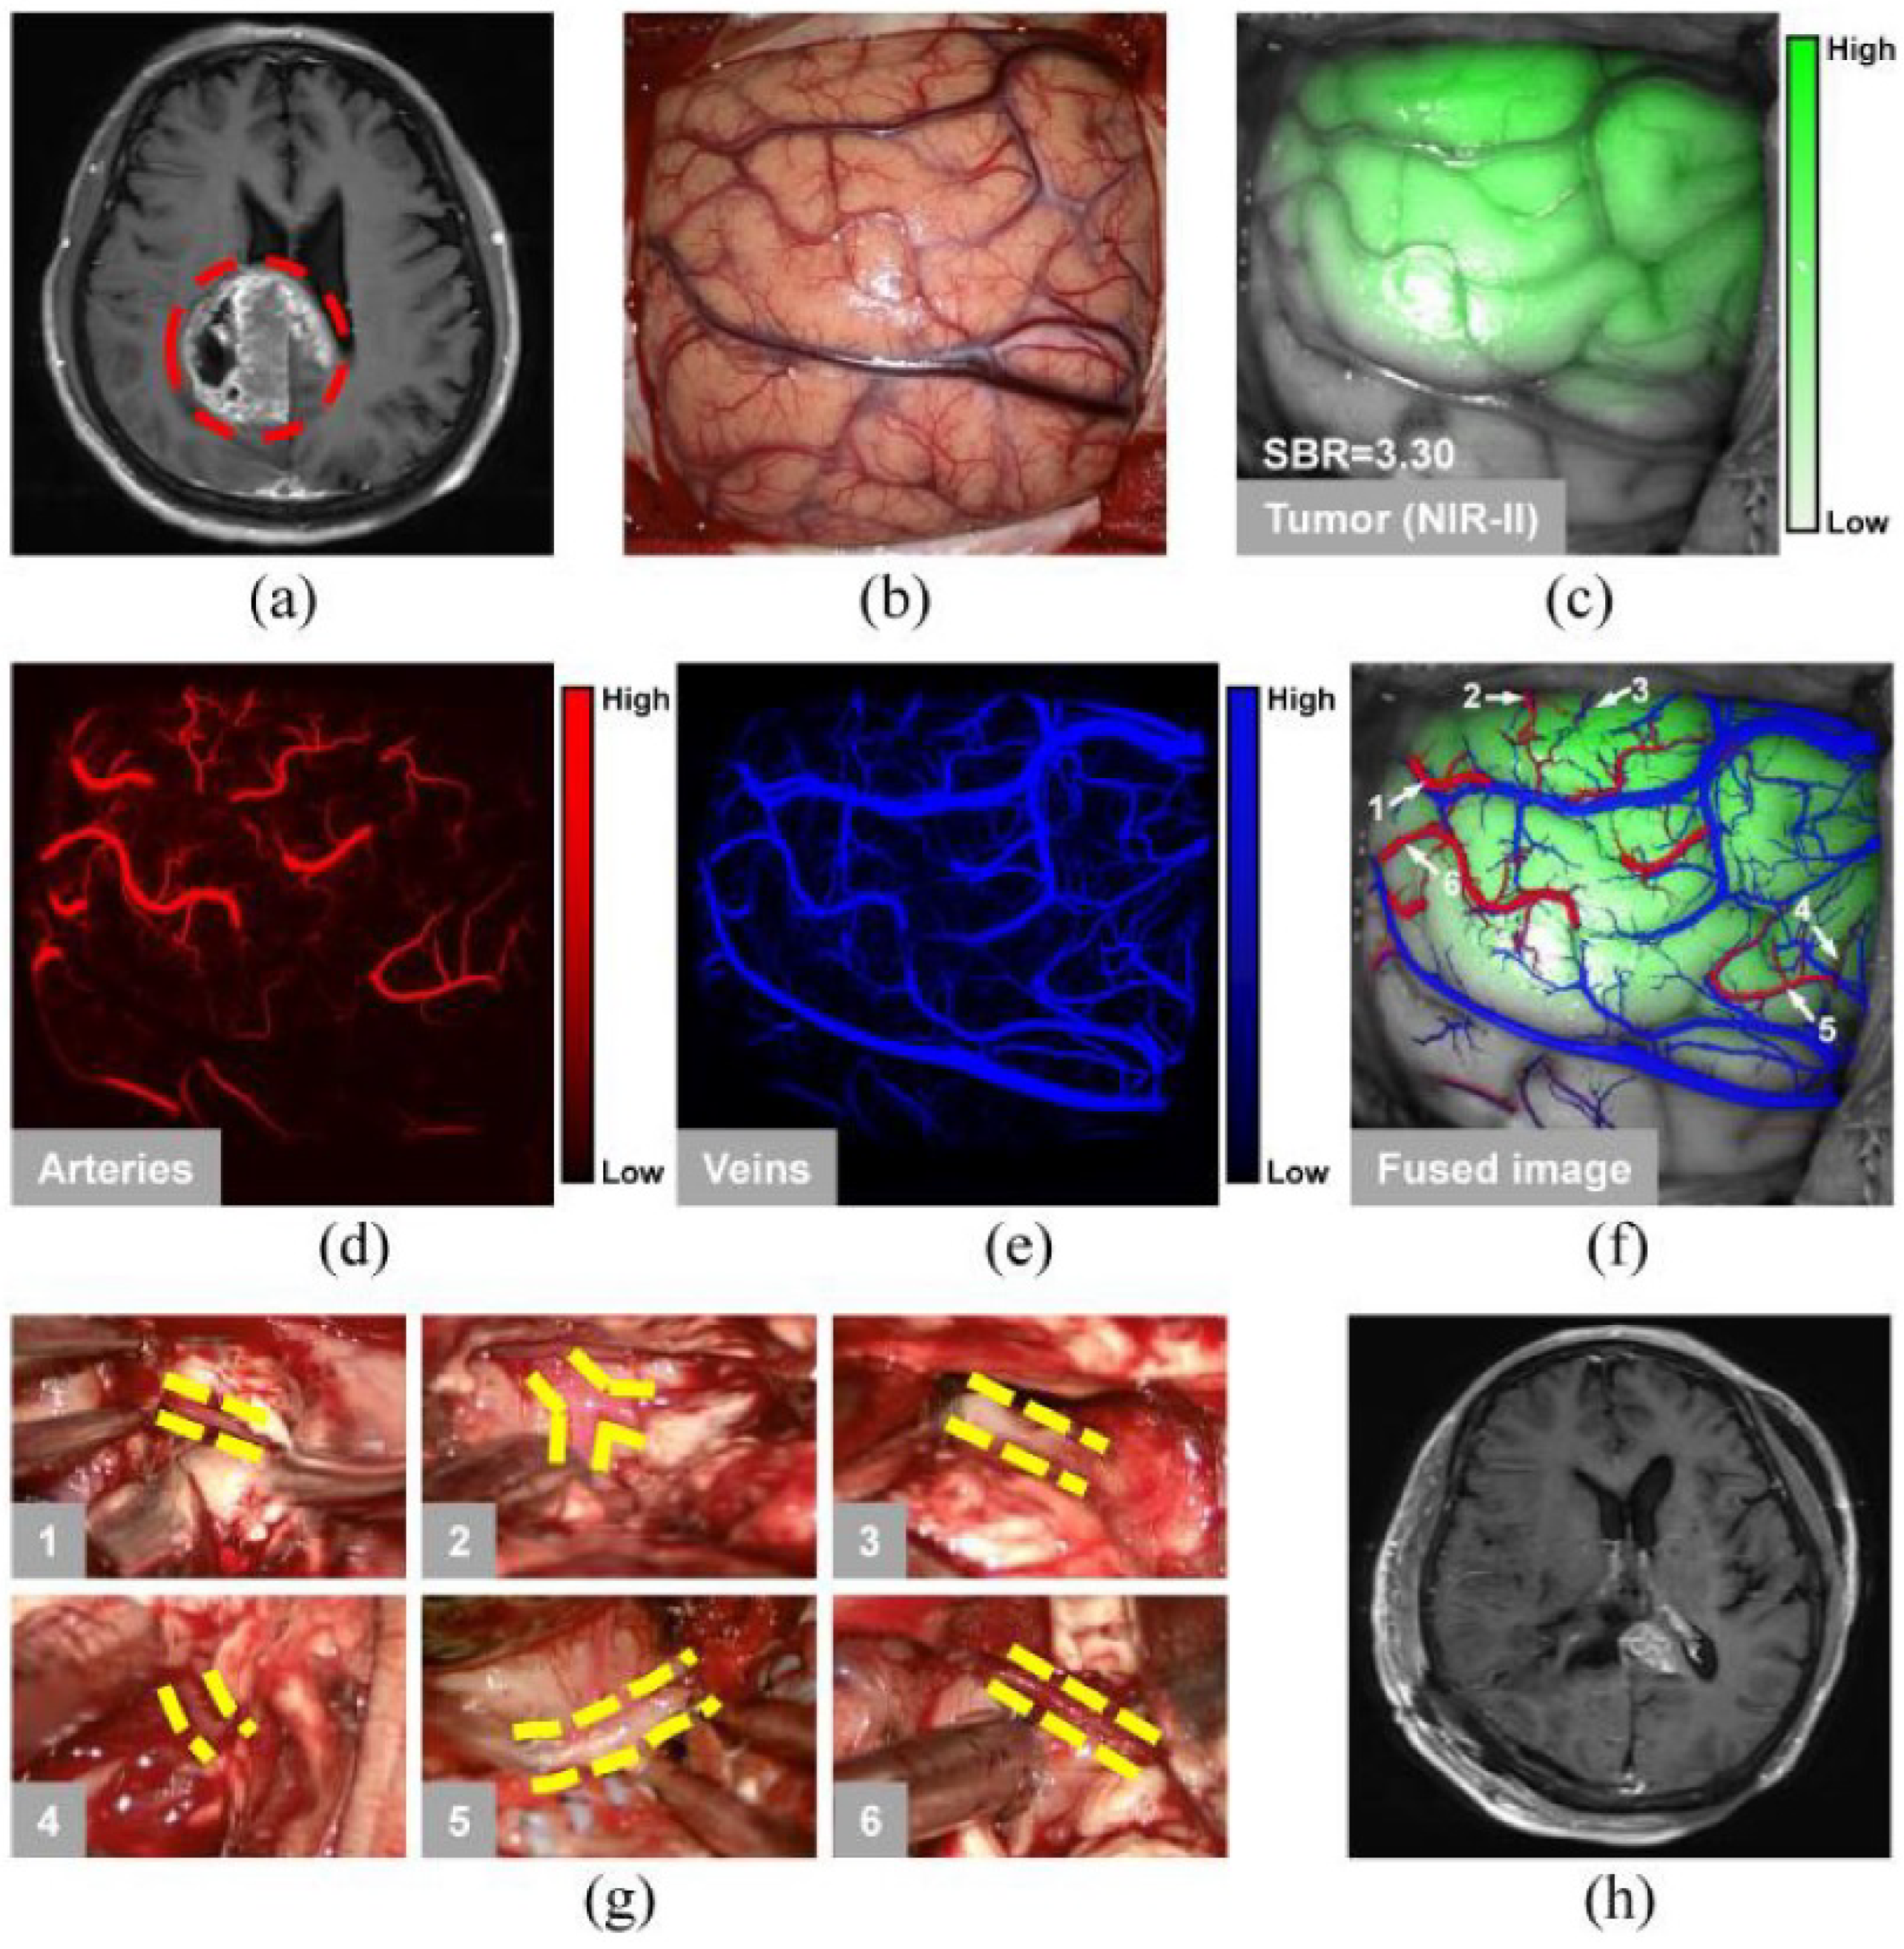

- Cao, C.; Jin, Z.; Shi, X.; Zhang, Z.; Xiao, A.; Yang, J.; Ji, N.; Tian, J.; Hu, Z. First clinical investigation of near-infrared window IIa/IIb fluorescence imaging for precise surgical resection of gliomas. IEEE Trans. Biomed. Eng. 2022, 69, 2404–2413. [Google Scholar] [CrossRef] [PubMed]